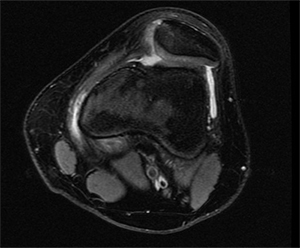

Because of the limitations of physical exam alone, imaging is also used to assist in making a diagnosis; a lateral plain film can show three common signs of trochlear dysplasia: presence of a supratrochlear spur, crossing sign and double contour sign. Taken together these findings allow for classification according to the Dejour system [7]. A standard knee series of plain radiographs (x-rays) will show if there is a fracture of the patella or if there are other malalignment which may contribute to patellar instability or recurrent instability. Other important studies include a magnetic resonance image (MRI). This is typically ordered after an initial dislocation to ensure that there is not a cartilage fracture which could potentially be repaired. Furthermore, early MRI will show damage to the tissues that may be more difficult to see once swelling and inflammation recede. Computed tomography (CT or CAT scan) is not usually required for diagnosis, but can be obtained to confirm the type of dysplasia into one of four Dejour categories and perform other measurements which are useful in preoperative planning for reconstruction once the decision for surgery has been made [7]. Measurements of valgus alignment, sulcus angle, and tibial tubercle-trochlear groove distance help determine what type of corrective procedure is required and what degree of correction is needed.